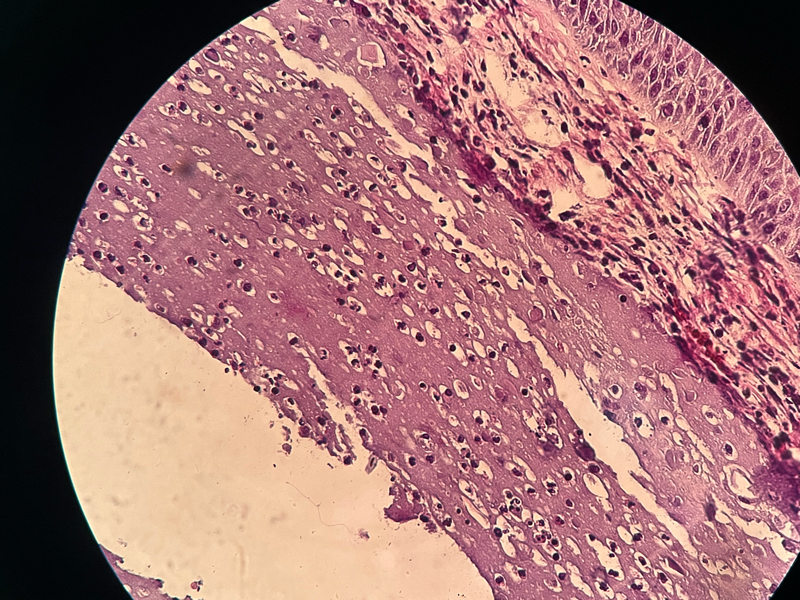

臀部肿物

发现臀部肿物半年,红肿破溃

皮肤肿物一个,大小约2.2✖️1.6✖️0.7cm ,突出于皮肤,肿物表面灰红灰白,切面灰白,质略硬

肿瘤样钙盐沉积症?

钙化上皮瘤?

瘤样钙质沉积症。